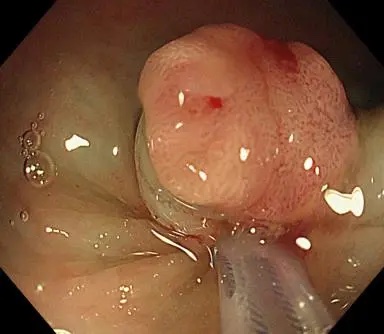

染色放大观察

手术切除

听到“早癌”,患者顿时就慌了。刘哲安慰道:“早期消化道肿瘤,不用开刀也能治愈,而且治愈率能达到95%以上,通过内镜下微创治疗即ESD术(内镜下粘膜剥离术)切掉肿物进行病理化验,如病理没有问题,切缘又很干净,就不需要再追加外科手术治疗。”听完刘哲的话,患者放宽了心,同意了手术方案。住院后,刘哲又为患者完善了放大内镜和超声内镜检查,进一步证实了病变性质和深度,决定实施直肠息肉粘膜切除术(EMR),不过数分钟,肿物就被顺利完整切除。